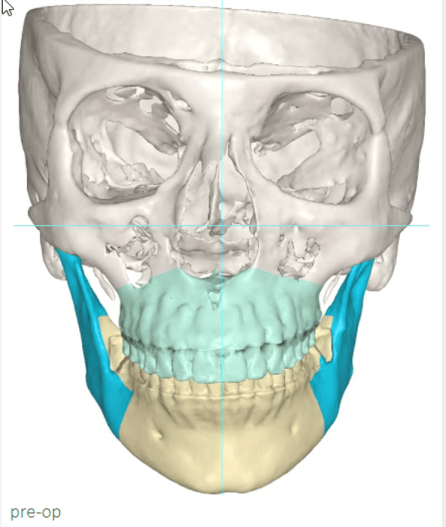

Nach diesem Befund entschied sich die Pa­tientin für eine umfassende Rehabilitation mit kombinierter kieferorthopädisch-kieferchirurgischer Therapie (Abb. 8a+b).

Nach acht Monaten Aligner-Therapie erfolgte die bimaxilläre Umstellungsosteotomie (Abb. 9a+b).

In der Frontalansicht ist eine leichte links-laterale Abweichung des Unterkiefers von der Schädelmitte zu erkennen (Abb. 29). Nach chirurgischer Analyse wurde die Laterognathie weitgehend ausgeglichen und der UK in CranioPlan zentrisch ausgerichtet (Abb. 30a–c).